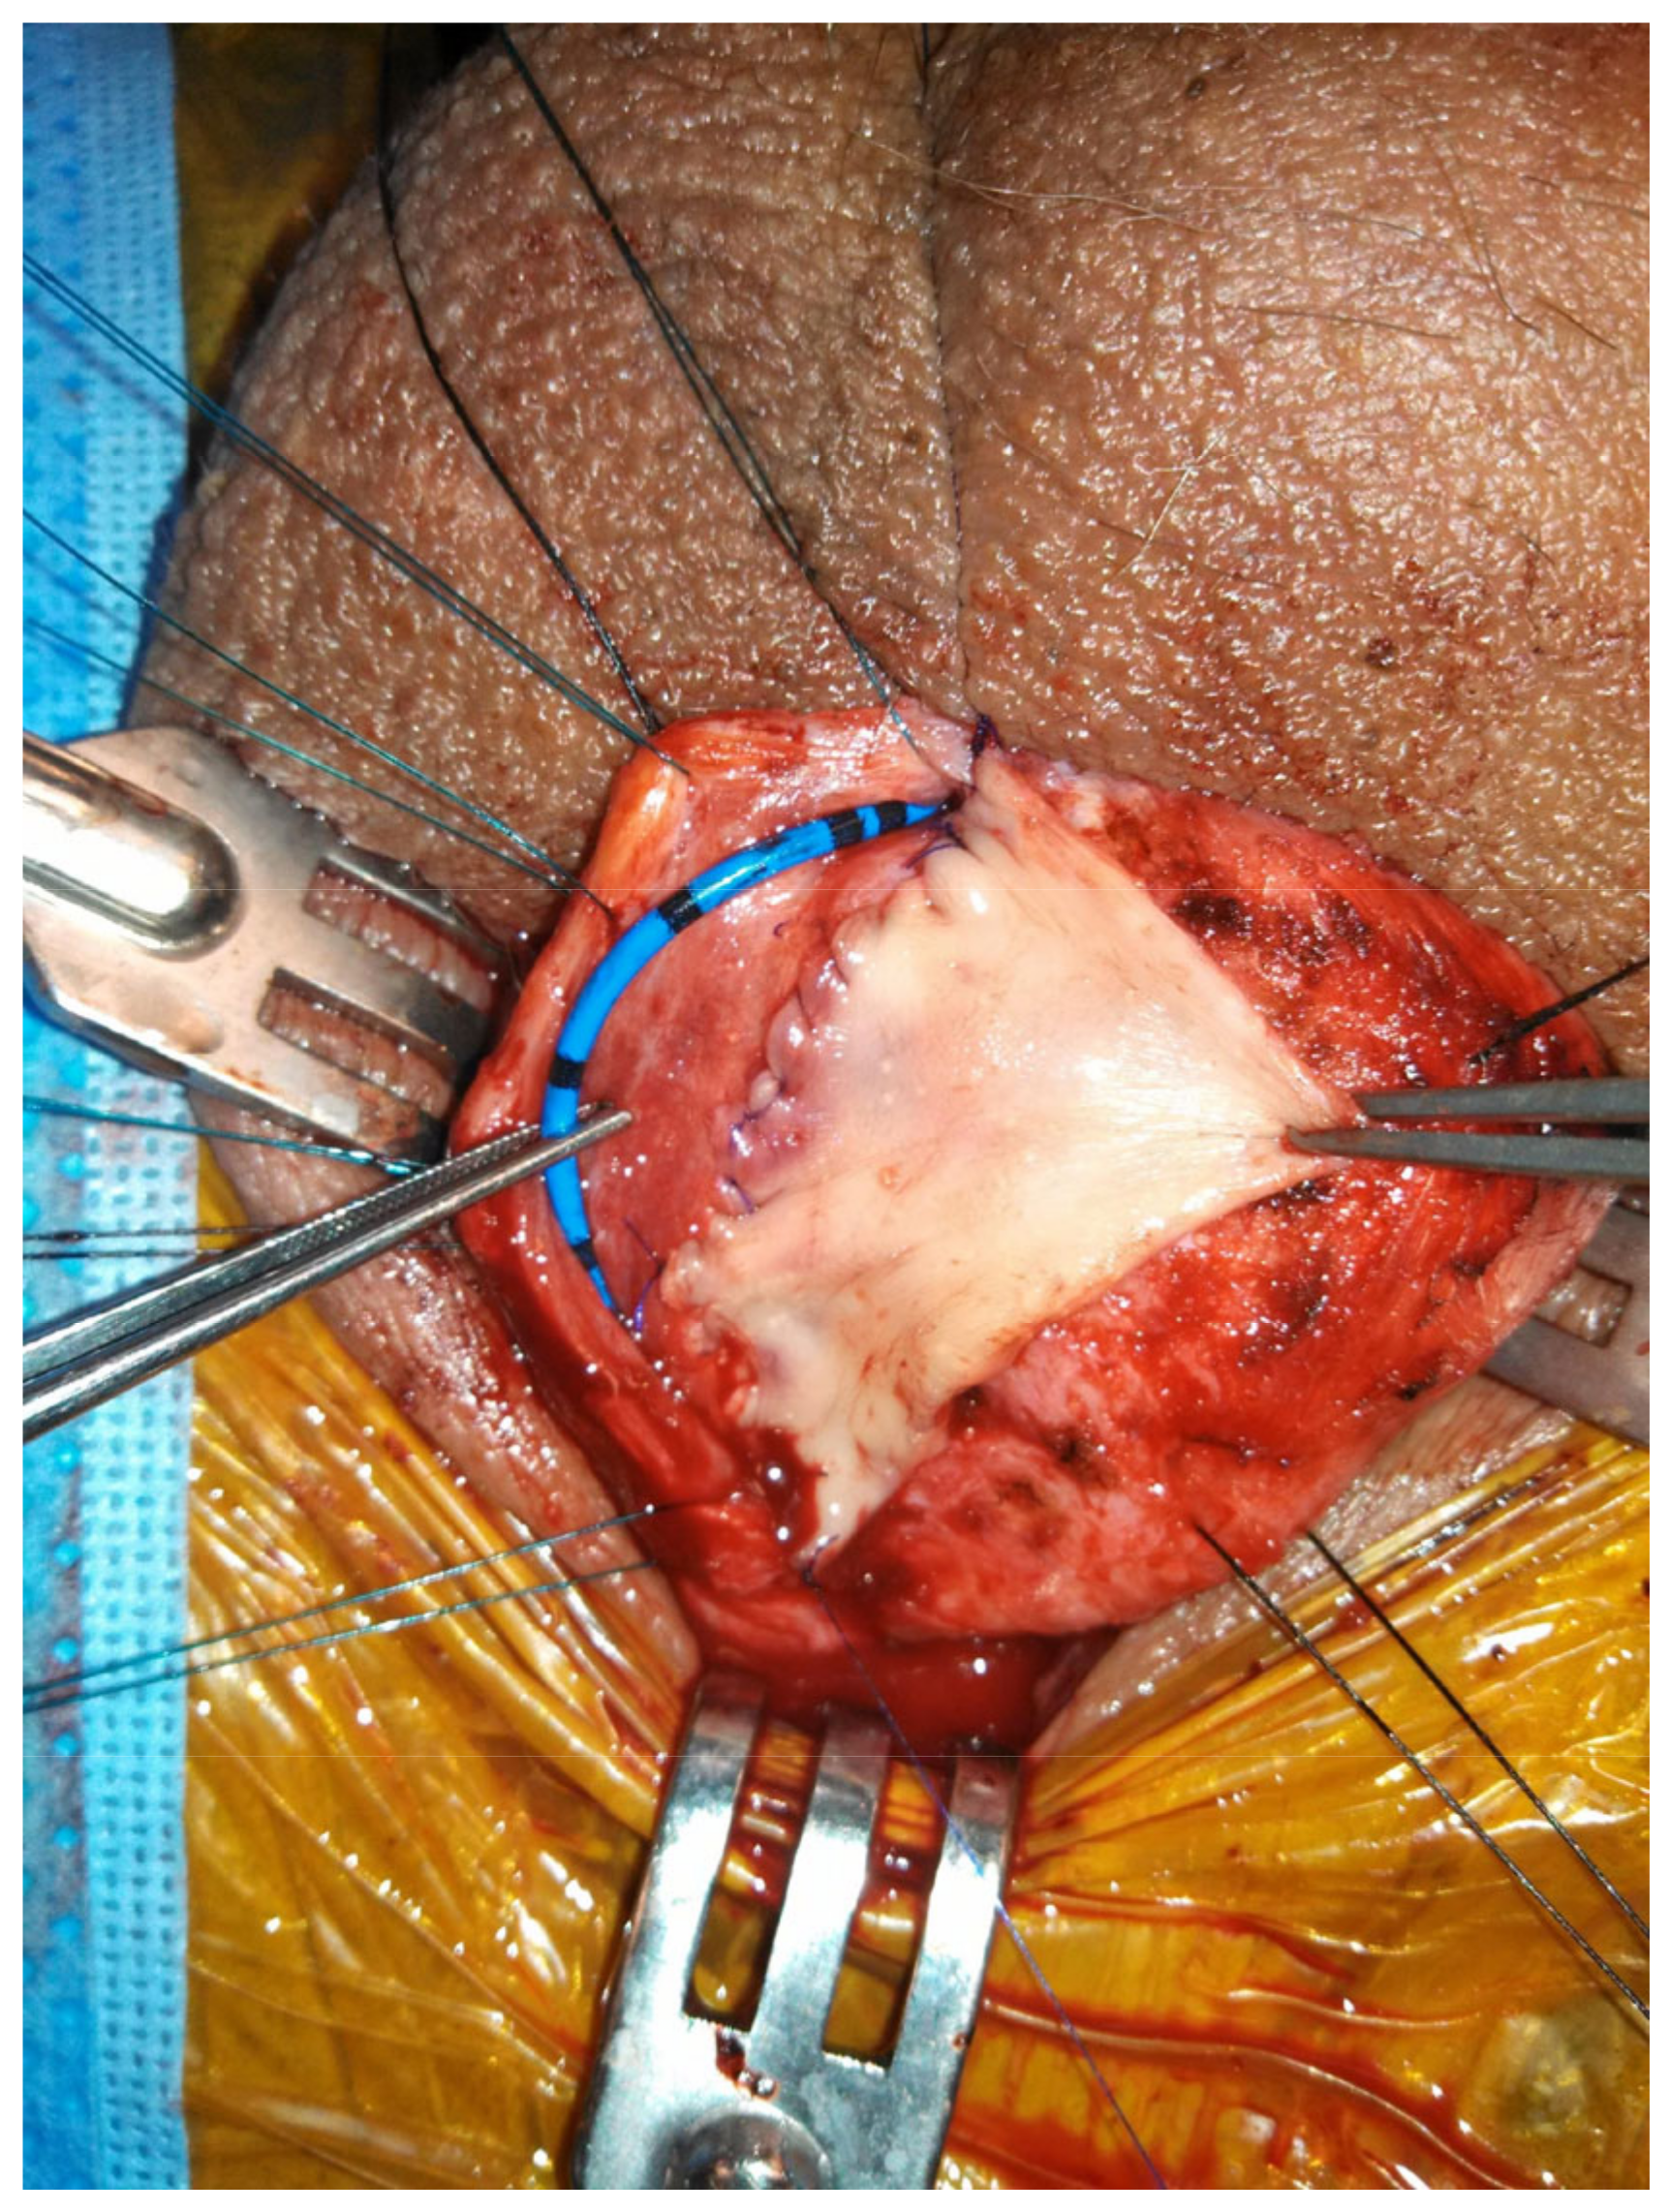

When the bulbar stricture is long (>2 cm) and non-obliterative, a dorsal onlay urethroplasty can be performed. Initially described by Barbagli in 1996, the technique has been modified over the years and has been shown to have durable success rates [29]. Dorsal graft placement has the benefit of strong corporal fixation, thus reducing risk of sacculation (Figure 2). There is also less operative blood loss due to the thinner bulbospongiosus dorsally. Ventral onlay described by Morey and McAnnich is also an option with durable success [30]. This option is preferred by some when the exposure is challenging due to proximal stricture location or obesity.

Figure 2.

Non-transecting, dorsal onlay buccal mucosal graft urethroplasty.